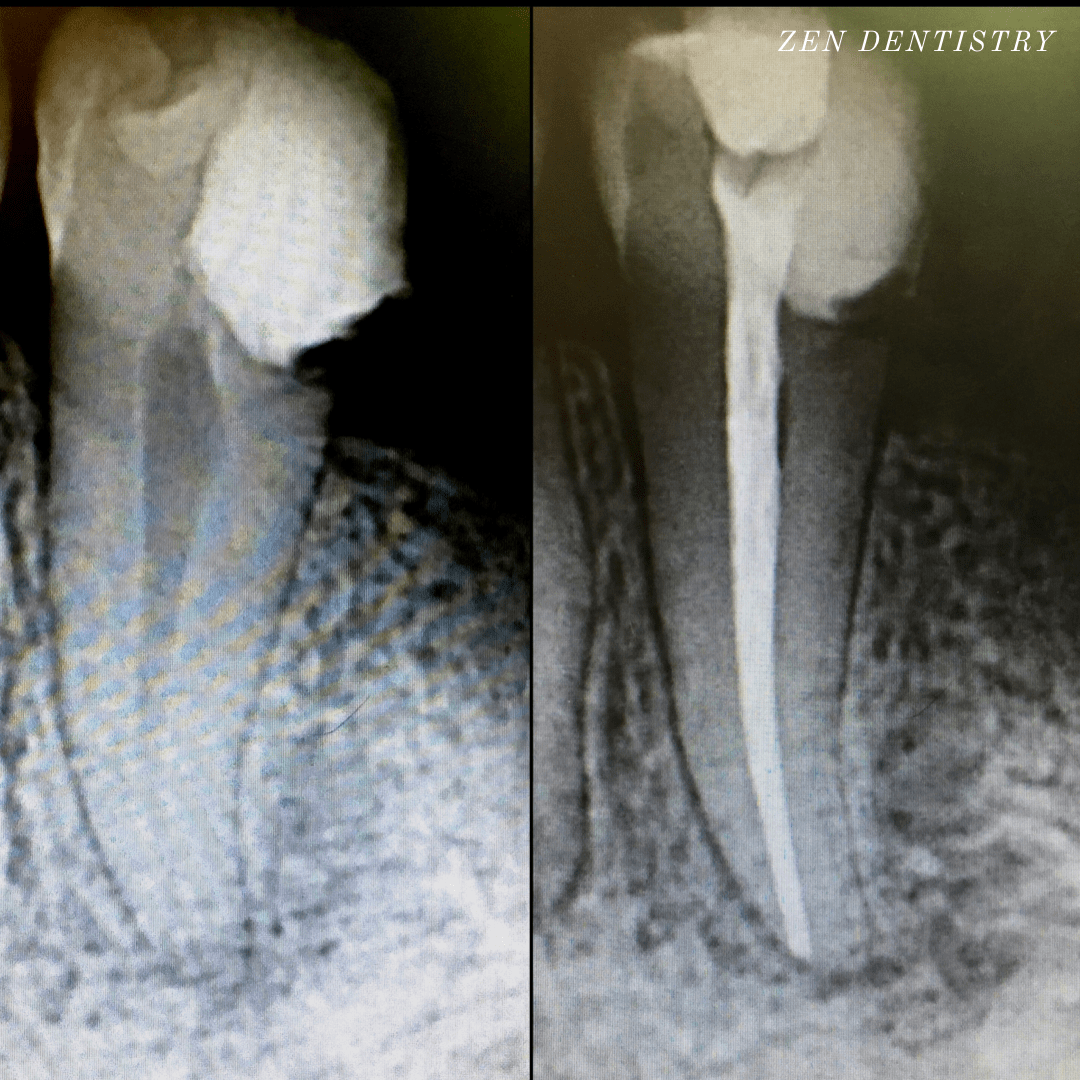

Patient presented to the office with a concern that the tooth has been causing severe constant pain that would become worse at night time and biting.